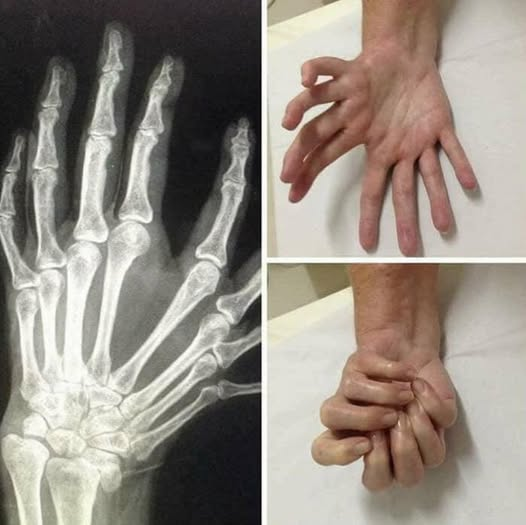

The first ever X-ray image was taken in 1895 by Wilhelm Röntgen, awarded the first Nobel Prize in Physics, 1901. The image of his wife Bertha’s hand (wedding ring clearly visible) propelled Röntgen into an international celebrity. Röntgen named the discovery X-rays, after the mathematical term ‘X’ which denotes something unknown. (Photo and caption by Nobel Prize Institute)